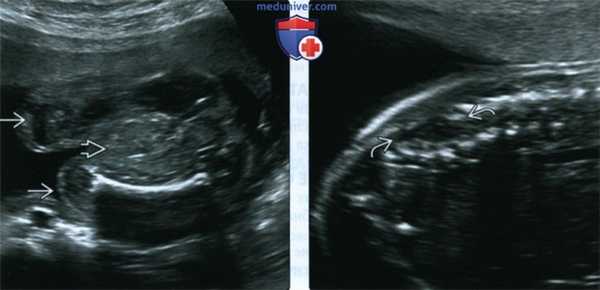

(Слева) УЗИ малого таза, поперечная плоскость. Между ног плода визуализируется толстая кишка В Наполненный жидкостью мочевой пузырь, анальная ямка и наружные половые органы не определялись. Исследование внеклеточной ДНК показало женский пол плода. Иногда данных УЗИ недостаточно для определения пола плода с клоакальной экстрофией. Наибольшие трудности сопряжены с реконструкцией мужских гениталий.

(Справа) УЗИ дистального отдела позвоночника, сагиттальная плоскость. Визуализируется закрытый (покрытый кожей) дефект нервной трубки. Аномалии развития позвоночника входят в структуру комплекса OEIS (буква «S»).